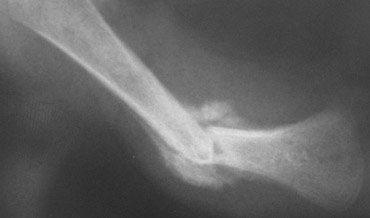

279 ) A 14 month-old child is brought by her concerned father to the Emergency department with a history that the child slipped out and fell on the ground from a table that is 10 feet in height. He says the accident occurred last night when he let the child stand on the table. The child cries when the right thigh is touched and does not move the right lower extremity. Rest of the physical examination is normal. There are no suspicious bruises or contusions on the skin. An x-ray of the right femur is shown below.

A skeletal survey is obtained and does not show any other fractures. There are no skull fractures or retinal hemorrhages or neurological deficits.

Based on the x-ray findings and the history, which of the following is the most likely diagnosis?

A) Osteogenesis Imperfecta

B) Fibrous Dysplasia

C) Accidental Injury

D) Child Abuse

E) Pathological Fracture from Ewing Sarcoma

Filed under: Uncategorized, USMLE Test Prep | Tagged: aRCHER ORTHOPEDICS, archer pediatrics, USMLE STEP 3 ORTHOPEDICS, USMLE STEP3 PEDIATRICS | 17 Comments »